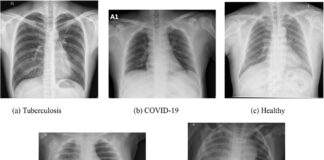

Jak wygląda zapalenie płuc na zdjęciu RTG? Zacienienia, nacieki i zagadki,...

Zapalenie płuc na RTG klatki piersiowej objawia się zacienieniami, konsolidacjami i naciekami w miąższu płuc. Typowe są homogenne zmiany lobarne, przede wszystkim w dolnych...